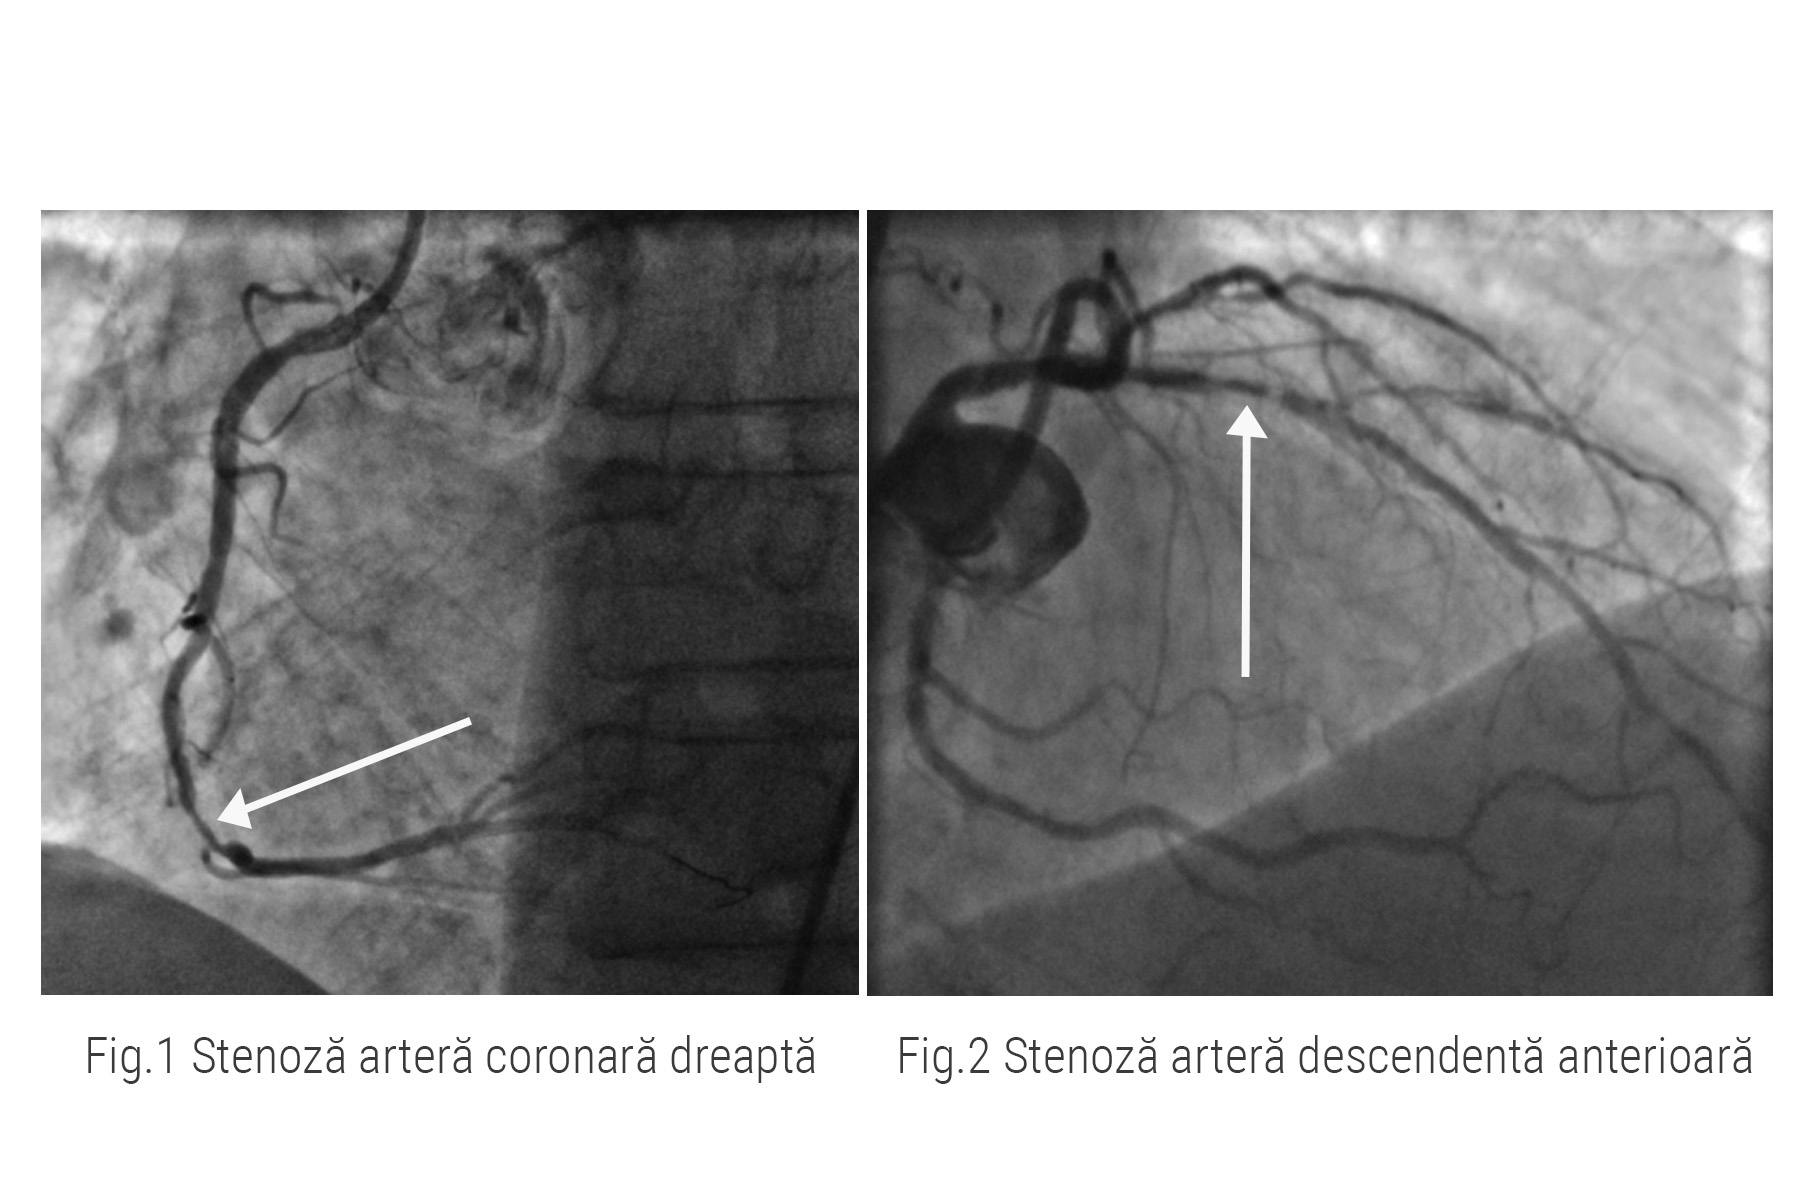

Doctorul Nicolae Cârstea, medic cardiolog intervenționist la ARES Constanța, a efectuat coronarografia și a conluzionat că pe artera coronară dreaptă exista o depunere semnificativă de grăsime (fig 1), iar pe artera descendentă anterioară există o îngustare de 95% a vasului de sânge (fig.2).

Practic, 5% din vasul respectiv era folosit pentru irigarea mușchiului inimii. Fără tratament, pacientul risca un eveniment cardiac major, un infarct miocardic acut care i-ar fi putut pune viața în pericol.

Pentru a reda circulația sângelui în artera coronară dreaptă, doctorul Nicolae Cârstea a efectuat dilatarea cu balon și ulterior, implantarea de stent. Rezultatul se poate vedea în imaginile de mai jos.

Rezultatul procedurii prezentate astăzi este un succes ceea ce înseamnă că pacientul nostru este în afara pericolului de a suferit un infarct miocardic(fig.4, fig.5).